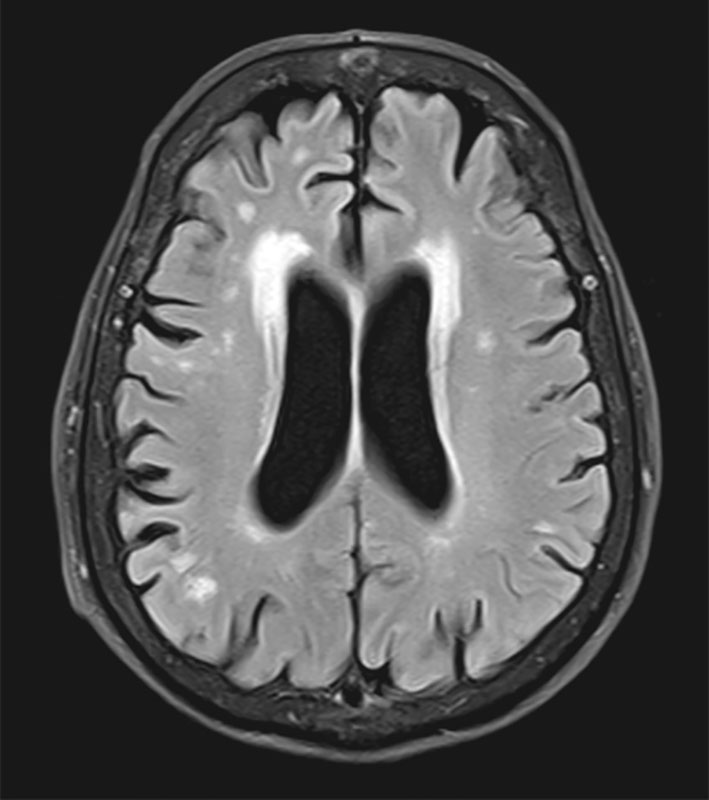

Fazekas grades. Лейкоареоз Fazekas 1 что это. Перивентрикулярный лейкоареоз мрт. Лейкоареоз юкста. Глиоз мозга мрт.

Fazekas grades. Лейкоареоз Fazekas 1 что это. Перивентрикулярный лейкоареоз мрт. Лейкоареоз юкста. Глиоз мозга мрт.

Fazekas grades. Лейкоареоз головного мозга мрт. Лейкоареоз 2 степени по Fazekas. Очаги микроангиопатии в веществе головного мозга Fazekas Grade 1. Лейкоареоз 3 степени по Fazekas.

Fazekas grades. Лейкоареоз головного мозга мрт. Лейкоареоз 2 степени по Fazekas. Очаги микроангиопатии в веществе головного мозга Fazekas Grade 1. Лейкоареоз 3 степени по Fazekas.

Fazekas grades. Fazekas 2. Лейкоареоз головного мозга мрт. Лейкоареоз Fazekas 1 что это.

Fazekas grades. Fazekas 2. Лейкоареоз головного мозга мрт. Лейкоареоз Fazekas 1 что это.

Fazekas grades. Перивентрикулярный лейкоареоз мрт. Перивентрикулярный лейкоареоз головного мозга мрт. Лейкоареоз Fazekas 1 что это. Лейкоареоз на кт.

Fazekas grades. Перивентрикулярный лейкоареоз мрт. Перивентрикулярный лейкоареоз головного мозга мрт. Лейкоареоз Fazekas 1 что это. Лейкоареоз на кт.